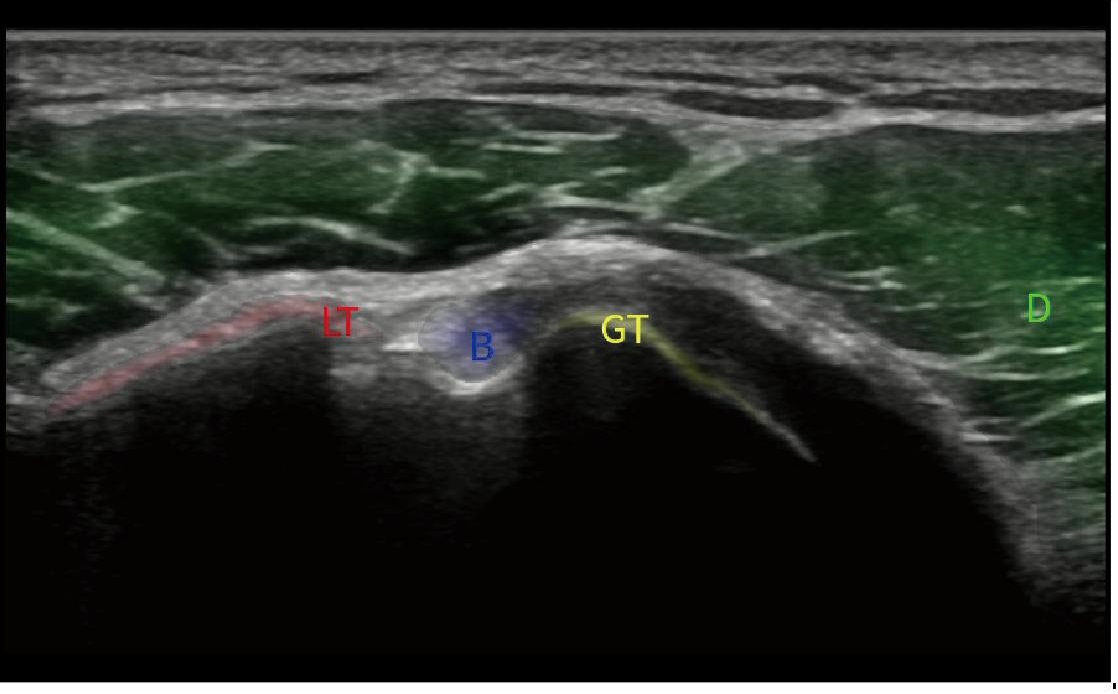

STIC

Zamansal ve mekânsal boyutlar boyunca frame ratelerin ortalamasını alarak, STIC farklı düzlemlerde görüntüler oluşturur; böylece hızla hareket eden fetal kalp yapılarını farklı açılardan kapsamlı bir şekilde inceleme ve değerlendirme olanağı sağlar.